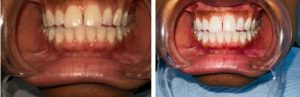

- Edentulism (Total Tooth Loss)

Edentulism, or complete tooth loss, is typically the result of untreated dental caries and advanced periodontal disease over a lifetime. Trauma or other conditions can also contribute.

Globally, about 7% of adults aged 20 years and older experience total tooth loss. Among adults aged 60 years and above, this prevalence rises sharply to 23%. Tooth loss can significantly impact nutrition, speech, self-esteem, and overall quality of life.